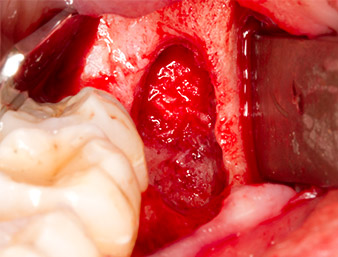

After block and local anaesthesia, the operating site was opened up and the soft tissue exposed for buccal retromolar access (Fig. 3).

The tissue above the root remnant was not completely ossified and consisted for the most part of granulation tissue modified by inflammation (Fig. 4).